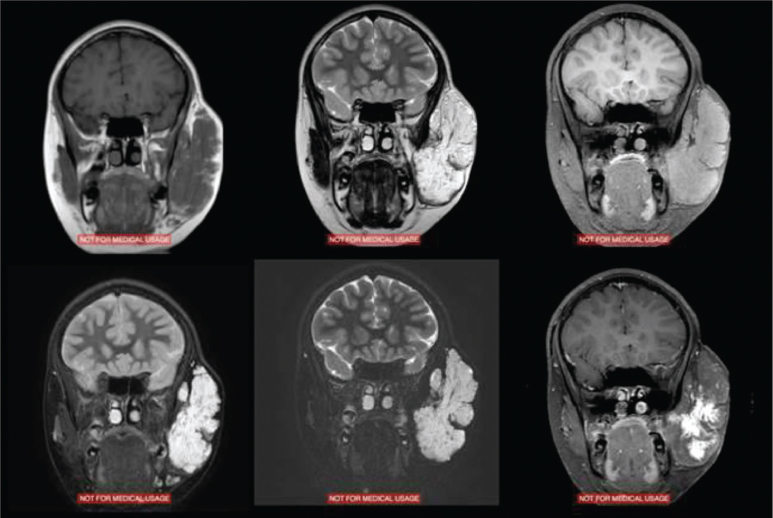

Most IHs are readily recognized by their characteristic clinical course and appearance, making further diagnostic testing rarely necessary. Imaging studies may be useful to evaluate for concomitant lesions, assess the full extent of a lesion that is not clinically visible, or occasionally lend support to an uncertain diagnosis. Ultrasonography can be helpful to examine for hepatic or abdominal IH in patients with multiple cutaneous lesions, or to evaluate the spine in patients with overlying lumbosacral lesions. Serial ultrasounds with and without color flow Doppler have been used to noninvasively monitor IH during growth or treatment when the lesion is not visible or has a significant deep component. However, clinical followup is more important than imaging. 23 Children with concern for PHACE syndrome should undergo imaging of the brain with magnetic resonance imaging (MRI) to evaluate for posterior fossa lesions, echocardiogram, and possibly angiography or magnetic resonance angiography to evaluate for aortic and cerebrovascular anomalies. When imaging is desired to determine the extent of the tumor, contrast-enhanced MRI is the modality of choice and provides excellent evaluation of soft tissue without exposing the patient to ionizing radiation. On MRI, proliferating IH appears as a distinct, lobulated, enhancing soft tissue mass that is isointense to muscle on T1 and hyperintense on T2 images, often with a visible feeding artery and draining veins and intralesional flow voids. 24 Involuting IHs are heterogeneous masses with areas of increased T1 intensity corresponding to fibrofatty tissue and less robust enhancement than proliferating lesions 25 ( Fig. 73.3 ). Again, imaging studies are rarely needed for diagnosis and treatment of uncomplicated IH.